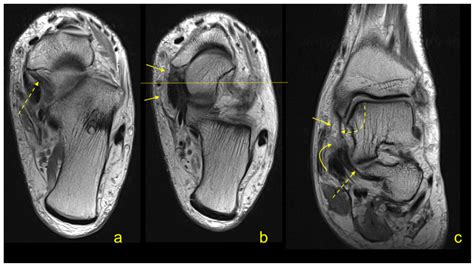

To diagnose issues related to the flexor retinaculum, medical professionals typically perform a physical examination. The Tinel’s sign test—tapping over the area of the retinaculum to elicit tingling in the foot—is a standard diagnostic indicator. Imaging studies such as Ultrasound or MRI are frequently used to visualize the thickness of the retinaculum and identify any cysts, scar tissue, or anatomical variations that may be contributing to nerve compression.